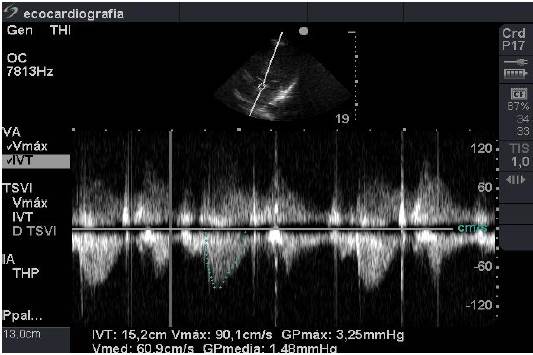

Se ubicó el transductor a nivel del ápex cardiaco, en la parrilla costal izquierda, bajo la mamila del mismo lado. Al orientar el transductor obtuvimos una imagen en 4 y 5 cámaras. En esta visión se realizaron las mediciones de la velocidad del tracto de salida con Doppler continuo, ya que en este lugar se logró una alineación paralela entre el flujo sanguíneo y el transductor, minimizándose la probabilidad de errores en la medición (Figura 5).

El gasto cardiaco se obtuvo midiendo flujo a través de esta área conocida.

Para obtener el flujo deberíamos poder medir todas las partículas que conforman la sangre, lo que es imposible. Para resolver este problema se midió con Doppler continuo la integral de la velocidad máxima del tracto de salida (IVT), en una ventana apical en cinco cámaras. Al multiplicar IVT por su área se obtuvo el volumen de eyección (VE) que se multiplicó por la frecuencia cardíaca (FC), obteniéndose el GC.